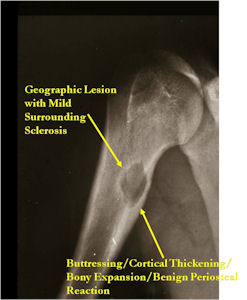

Plain X-rays:

- Geographic, circumscribed lesion usually around 5cm in size.

- There may be expansion of bone, cortical thinning and cortical breakthrough. A soft tissue mass may accompany this lesion but the soft tissue component is usually contained by the periosteum.

- The periosteum remains intact around the soft tissue component. Might need a CT scan to detect the subtle calcification (Egg Shell Rim of Calcification) associated with an intact periosteal reaction

- The lesion may be entirely radiolucent but usually shows some degree of mineralization. Mineralization may appear stippled like cartilage but do not see chondroid pathologically. Mineralization is sometimes better detected on a CT scan rather than an x-ray.

- Usually less surrounding sclerosis than an osteoid osteoma.